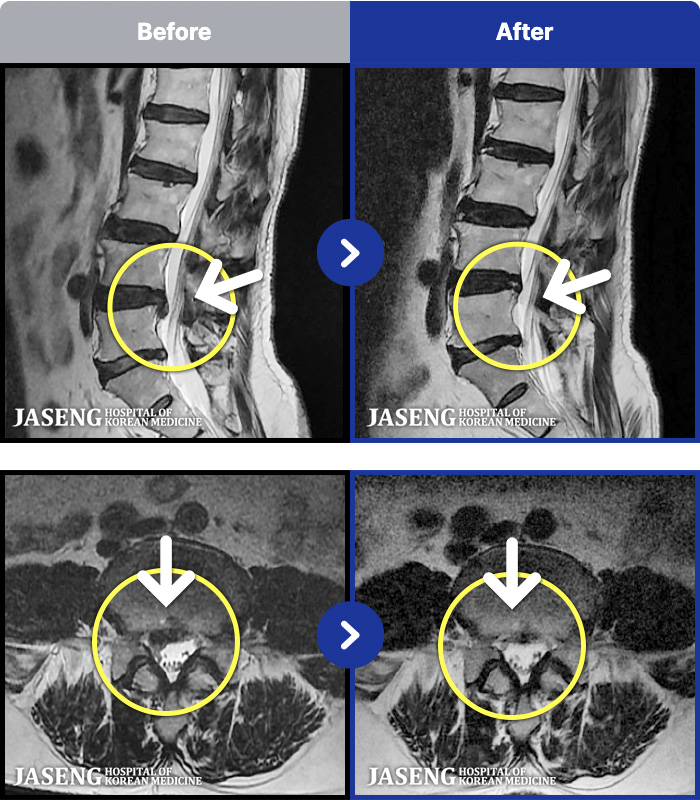

MRI ġ

1,240 MRI ũ ʸ Ȯϼ.

[_㸮ũ] 㸮 ϰ , ̾ ϼ̽ϴ.

[ϻ_㸮ũ] ϰ ӵǾϴ. ߰ Ͽ ߰ Ǵ ߵ ̻ ȣϴ ¿ϴ.

[λ_㸮ũ] 㸮 㸮 ̸ ִ.

[Ȼ_㸮ũ] 㸮 ְ ٸ ȱⰡ .

[_㸮ũ] 㸮 , ٸ ̾ ϼ̽ϴ.

[õ_㸮ũ] ߲ 㸮 , ٷ

[ϻ_㸮ũ] ݺ ӵǸ ڼ ÿ ȭǴ ߵ ̻ ȣϴ ¿ϴ.

[ϻ_㸮ũ] ؽϰ ߰ ̴ · ϻȰ ¿ϴ.

[ؿ_㸮ũ] 㸮 ϰ